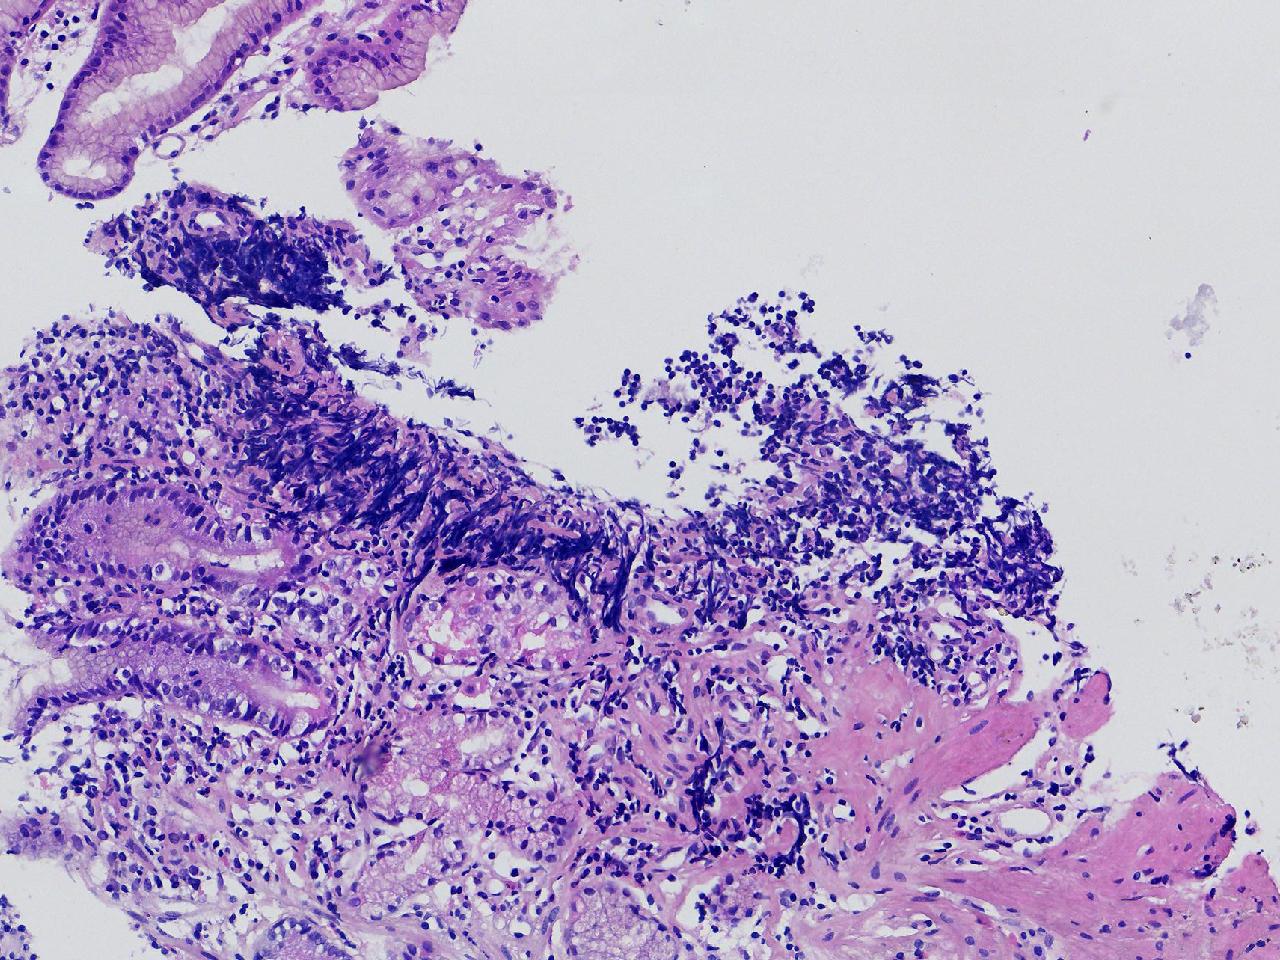

1.间质内淋巴组织有问题吗? 2.有没有低瘤变?

一般病史男,65岁,胃镜活检,胃窦粘膜红白相间,花斑样改变,大弯侧粘膜变薄,血管透见,可见多发片状充血糜烂灶及点状褐色物覆着,活检2块送检,质软弹性可。

标本名称胃窦活检

大体所见灰白色不整形软组织2块,直径均0.2厘米。

慢性萎缩性胃炎伴肠化,固有层淋巴细胞聚集

萎缩性炎,伴有肠化,淋巴组织挤压变形,感觉没有太大的问题。

炎性,无瘤变。